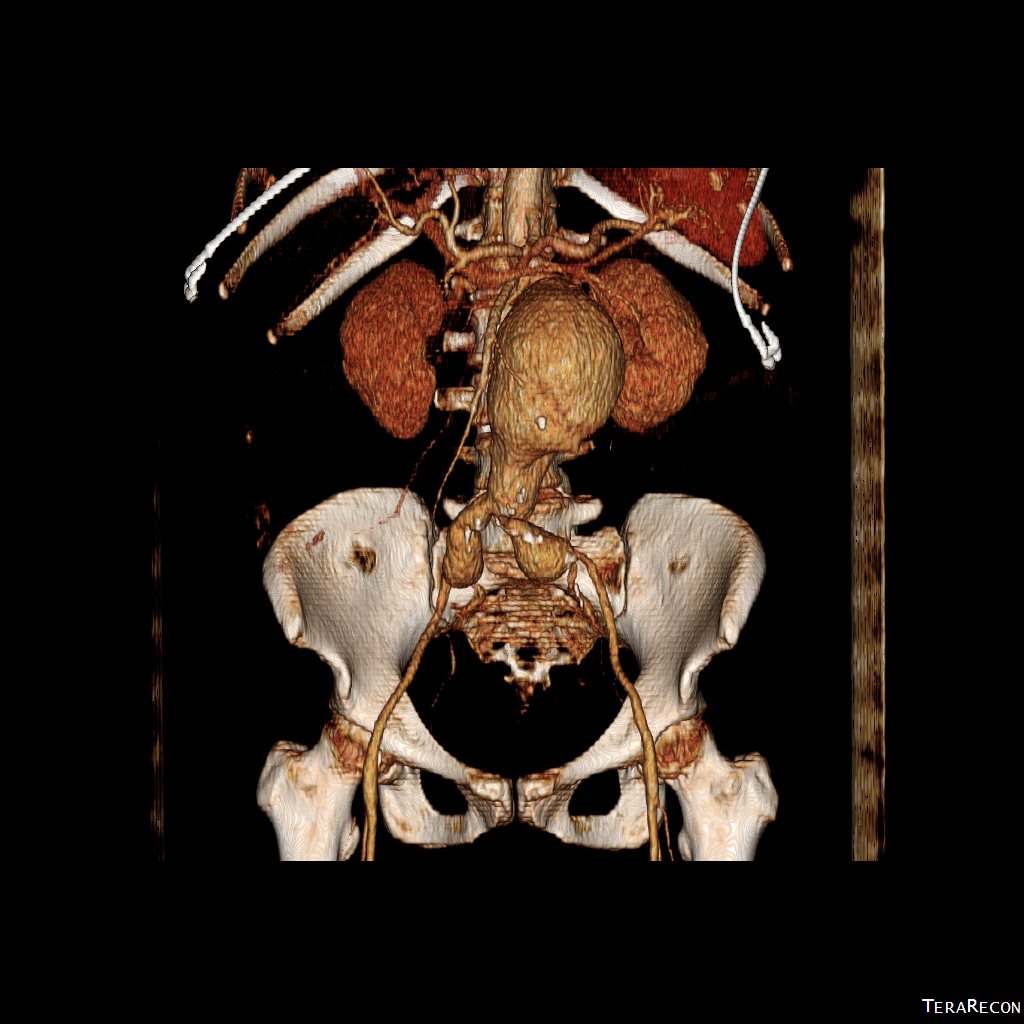

CT scan was performed showing an enlarging AAA over 8am and abundant retroperitoneal pancreatic fluid without abscess or infection. The AAA was infrarenal but complicated by a severely tortuous, short infrarenal neck with 90 degrees of angulation and about 8mm in length. As the pancreatic leak was yet early in the process, no pseudo aneurysms had formed. MRCP showed no active leak.

2. EVAR -This is outside the IFU for any of the available devices because of the highly tortuous neck anatomy. While note shown, the external iliac arteries were 5mm in diameter, but in the absence of plaque, was possibly due to spasm. The Nellix device is yet on trial, but there are limits on how much you can straighten this neck. The devices with suprarenal stents end up straightening out the graft with deployment of the graft in an ellipse. This also means loss of seal zone length which decreases with oblique deployment. FEVAR is not possible because of this neck tortuosity as well but was considered briefly.